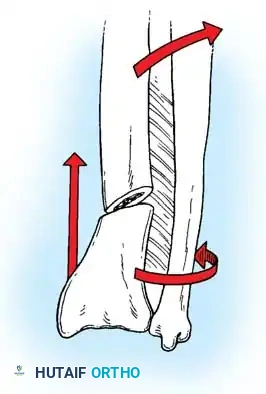

Biomechanics of the Tension Band:

The superficial (posterior) surface of the olecranon is the tension side of the bone. A figure-of-eight wire placed on this surface converts the tensile forces generated by the triceps into compressive forces across the articular fracture line, utilizing the humeral trochlea as a fulcrum.

Surgical Warning: A simple wire loop is biomechanically inferior to a figure-of-eight loop. If a simple loop is used—especially if its axis lies anterior to the mid-axis of the olecranon—the pull of the triceps will cause the fragments to separate posteriorly, leading to articular step-off and limited extension.